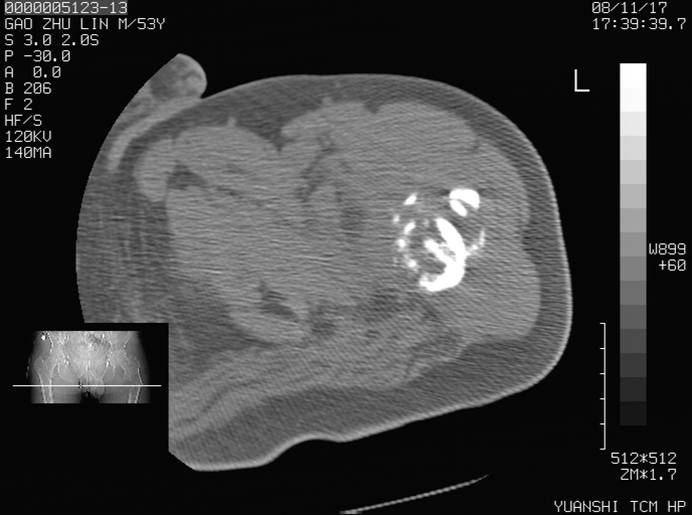

标题: CT16696:M53Y,左股骨上段骨折。 [打印本页]

标题: CT16696:M53Y,左股骨上段骨折。

左股骨上段外伤1个小时,左股骨上段疼痛。村医以腰椎间盘病变给以按摩及理疗数天。

图像不太清楚,左股骨上段外伤性骨折?病理性骨折?

左股骨上段粉碎性骨折

左股骨上段粉碎性骨折;建议上传骨窗看看是不是病理性的啊!

左股骨上段粉碎性骨折,不排除病理性骨折可能。

考虑骨肉瘤伴病理骨折

考虑:骨肉瘤伴病理骨折.

病理性骨折,考虑转移所致.